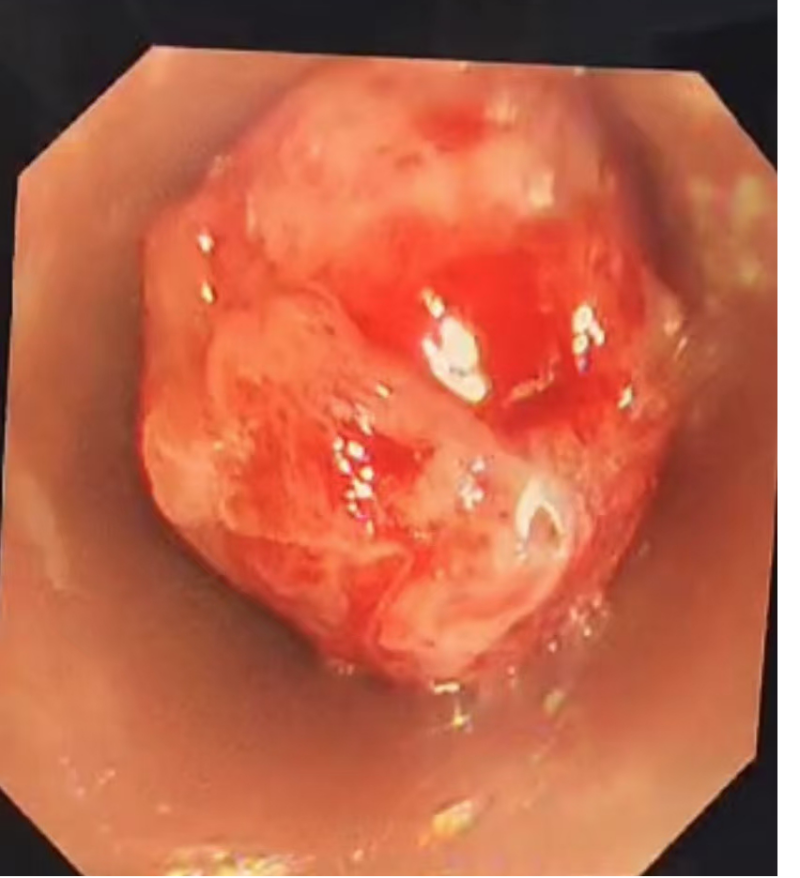

67岁的梁先生,因突发呼吸困难至当地医院就诊,急救车奔波两百公里送至南溪山医院呼吸与危重症医学科二病区,入科时,患者半卧位呼吸,口唇紫绀,静息状态下即感气紧,双肺闻及哮鸣音。立即完善检查发现气管内有肿物,堵塞管腔约80%,伴心肌标志物升高、高血压,心肺功能不全,死亡风险极高。

面对紧急情况,呼吸与危重症医学科二病区主任屈东明博士迅速组织麻醉科和内镜中心小组协助急会诊,带领呼吸介入团队李海斌副主任医师一起制定详细手术计划,决定采用全麻下支气管硬镜下肿瘤切除术,在支气管硬镜直视引导下,鞘管成功铲切下一大小约20X15mm肿物,术后患者呼吸困难明显缓解!梁先生终于又可以自由呼吸!